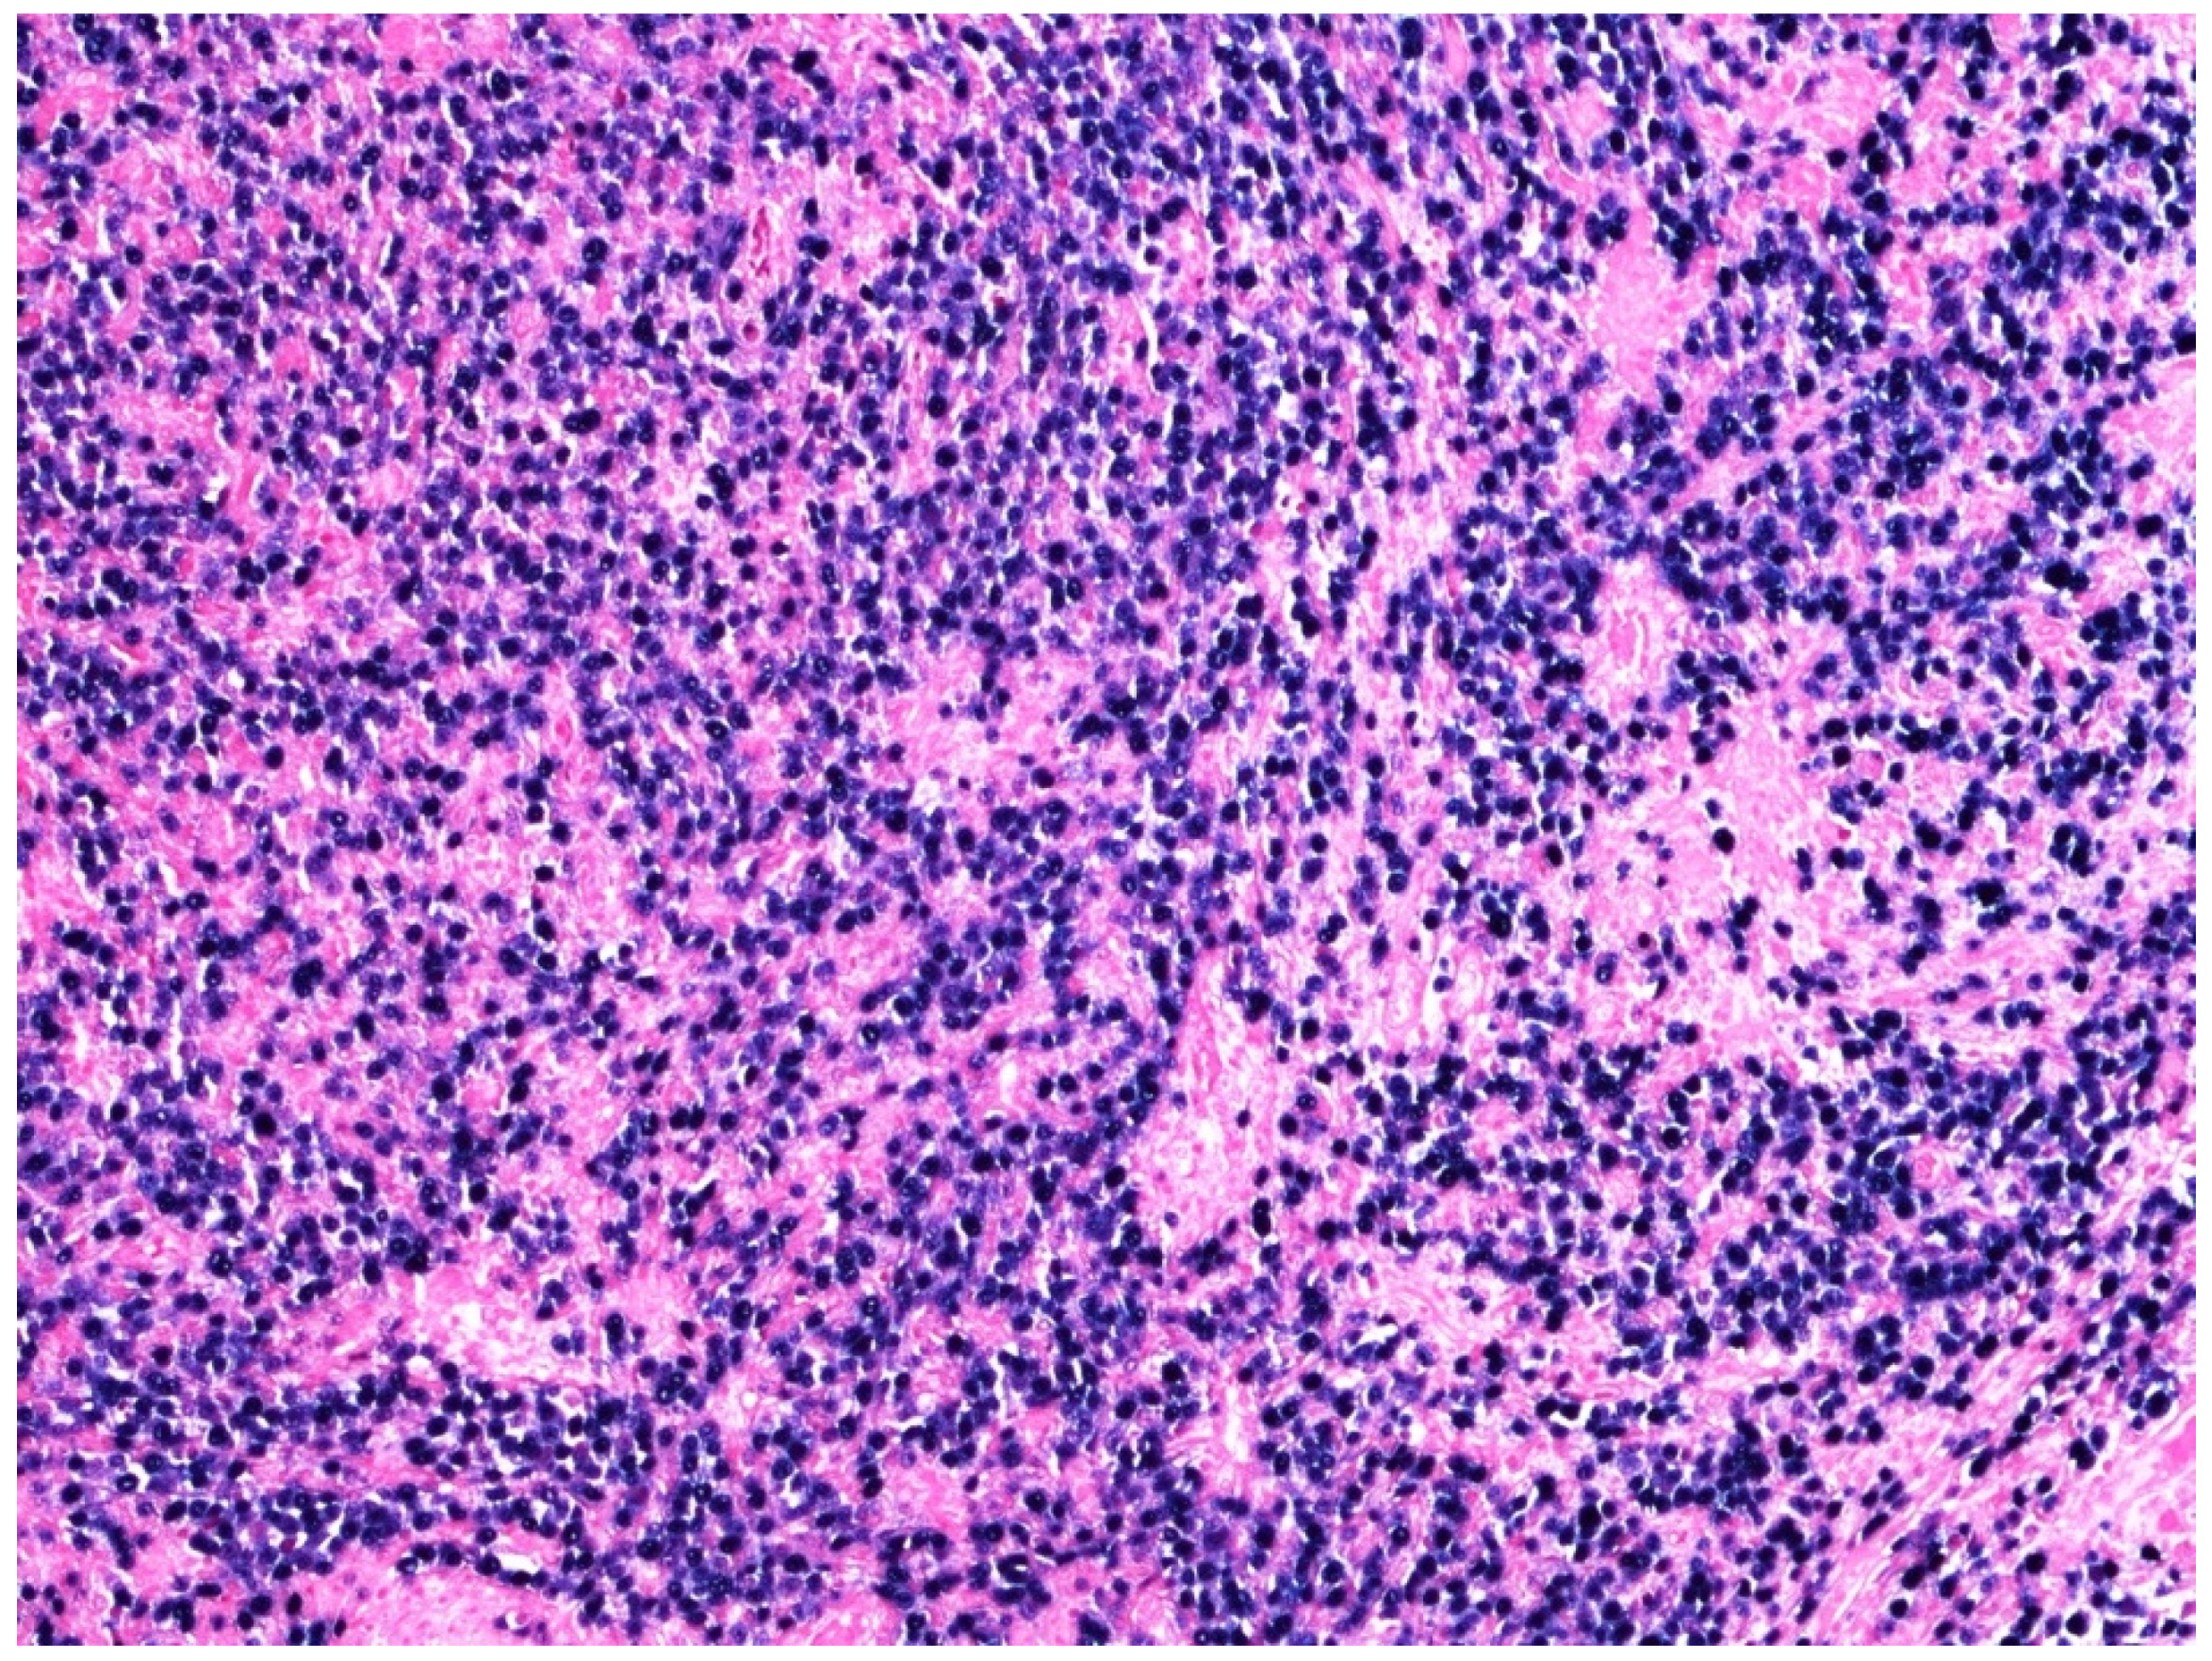

5. Histology, Immunophenotype, and Genetic Features of DLBCL, NOS

6. EBV-Positive DLBCL, NOS and Primary Bladder Lymphoma

7. Differential Diagnoses and Potential Diagnostic Pitfalls